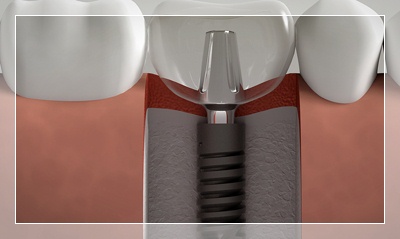

İmplantoloji

Eksik dişleriniz için en modern ve kalıcı çözüm. Titanyum implantlarla doğal diş görünümü ve fonksiyonu. Çekmeköy'de deneyimli kadromuzla implant tedavisi.